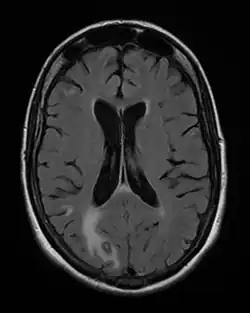

Toxoplasmosis in humans is diagnosed through biological, serological, histological, or molecular methods, or by some combination of the above.[63] Toxoplasmosis can be difficult to distinguish from several other conditions, especially ones that are common in HIV/AIDS and immunocompromised patients, and can cause central nervous system problems and brain lesions.[69] Toxoplasmosis is most commonly mistaken for primary central nervous system lymphoma, both conditions cause lesions in the brain, but in about 50-80% of cases the lesions appearances can be very similar on imaging, and exist in an area of the brain that makes biopsying too risky, however the main difference is lymphoma typically causes a single lesion in the subependymal region, and toxoplasmosis causes multiple lesions scattered through the basal ganglia.[70] Other conditions that can present as toxoplasmosis on a differential diagnosis are metastatic brain lesions, progressive multifocal leukoencephalopathy,[71] CNS tuberculosis,[72] bacterial or fungal brain abscess, cytomegalovirus (CMV),[73] and herpes simplex encephalitis.[69][74]

Lymph nodes affected by Toxoplasma have characteristic changes, including poorly demarcated reactive germinal centers, clusters of monocytoid B cells, and scattered epithelioid histiocytes.